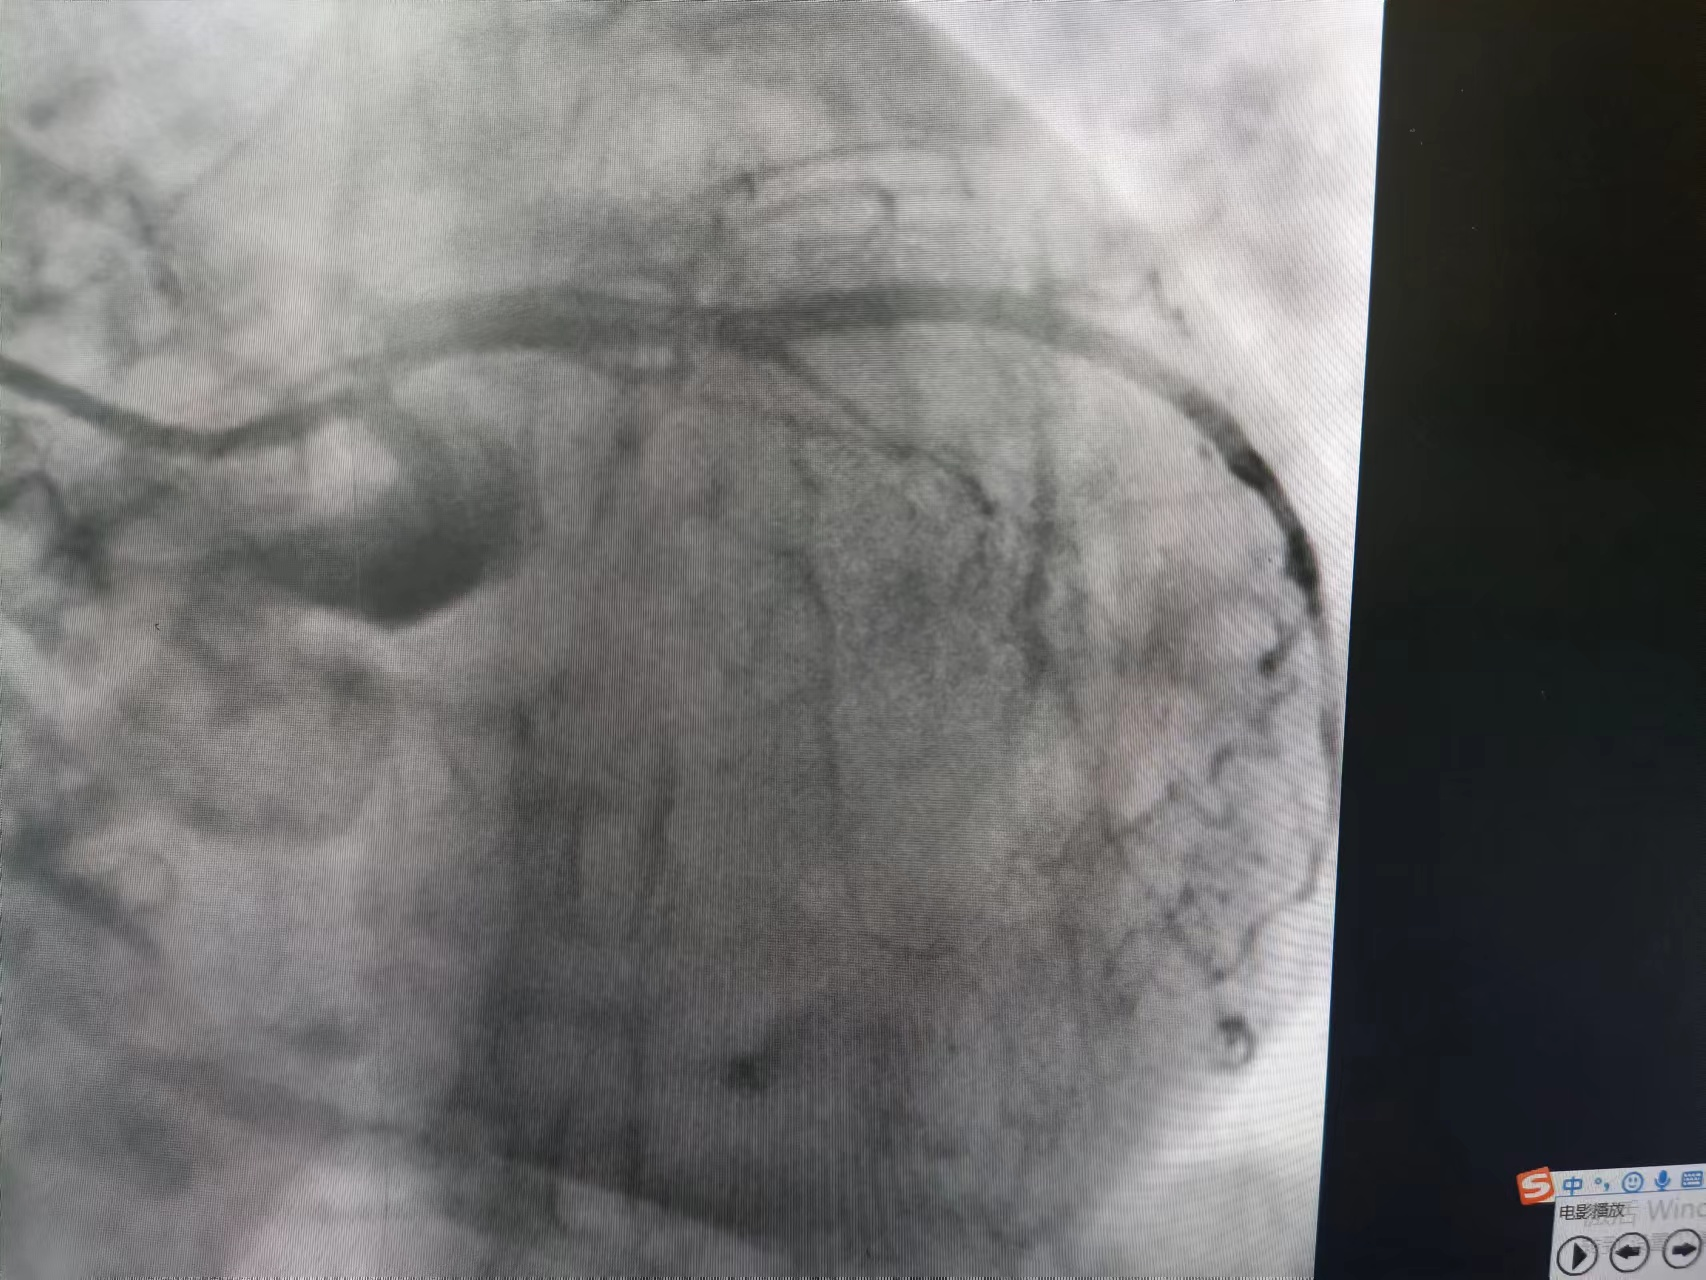

![]() 术后冠脉造影

植入支架发生慢血流

血流恢复